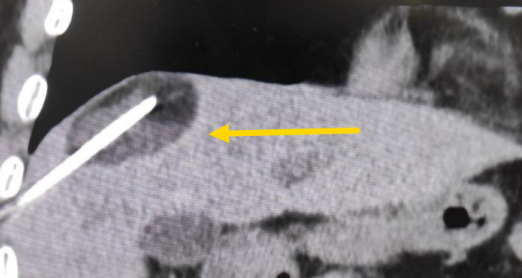

這個患者病變位置刁鉆,穿刺難度大,冷凍消融的難點在于既要不損傷膈肌和肺組織,同時又要盡最大可能完全消融腫瘤。術(shù)前陳寶瑩主任、李鐵柱教授、兀云飛醫(yī)生詳細(xì)設(shè)計進(jìn)針路徑、布針計劃,術(shù)中微創(chuàng)團(tuán)隊協(xié)調(diào)配合,李鐵柱教授仔細(xì)操作,精準(zhǔn)到位,順利完成兩個病變的布針,遂啟動治療,先快速降溫到-150多度,再升溫至15?,經(jīng)過兩個循環(huán)反復(fù),即刻觀察到病變完全被冰球覆蓋,同時周圍臟器無損傷,術(shù)中患者幾乎沒有疼痛,還和醫(yī)生聊起了天。

術(shù)中冰球形成